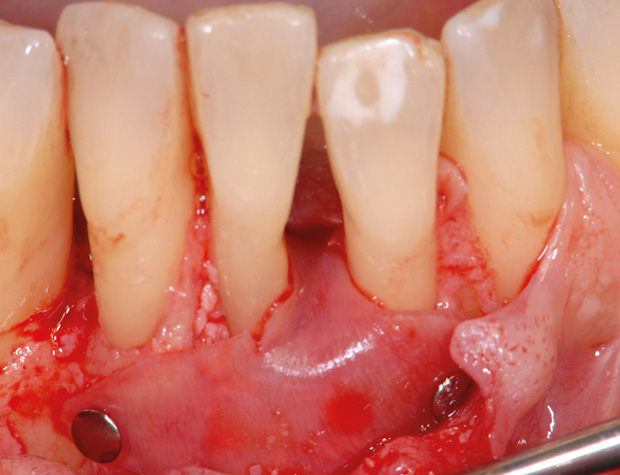

Nach der nicht-chirurgischen Parodontitis-Therapie verbleiben an stark parodontal-kompromittierten Zähnen häufig noch Resttaschen, die im Rahmen einer erfolgreichen Parodontitis-Therapie weiter behandelt werden müssen. Zu diesem Zeitpunkt stellt sich also die Frage, ob der einzelne Zahn mittels parodontalchirurgischer Verfahren erhaltungsfähig ist oder doch besser extrahiert werden sollte. Regenerative parodontalchirurgische Verfahren spielen an dieser Stelle eine große Rolle.Doch wann sollte welche chirurgische Technik, wann sollten welche regenerativen Materialien verwendet werden? Der Workshop vermittelt Kenntnisse, wann ein Zahnerhalt mittels Regeneration parodontaler Defekte erfolgreich möglich ist und wann welche chirurgischen Techniken und regenerativen Materialen zielführend sind.

Die Teilnehmer trainieren am Tiermodell verschiedene mikrochirurgische Techniken der Parodontalchirurgie. Zusätzlich werden die Schritte regenerativer Maßnahmen an unterschiedlichen Defekten (z.B. an 1-, 2- und 3-wandigenDefekten) mit den verschiedenen regenerativen Materialien geübt.